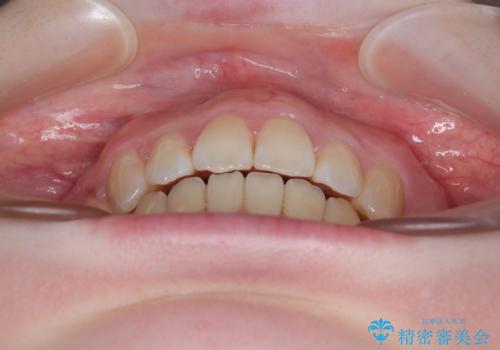

飛び出した上顎前歯 抜歯矯正で横顔の印象を改善

強い舌の突出癖により、上下前歯が前方に飛び出しており、特に上顎前歯は下顎よりも更に前方に位置している状態でした。